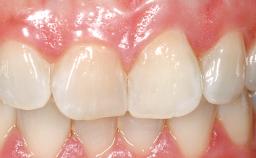

A 39-year-old male patient presented with a chief complaint of discomfort and gingival discoloration around his maxillary left central incisor. He was in good general health and was a non-smoker. His past dental history was significant because of the traumatic fracture of tooth 21 in a sporting accident at age 13. Initial dental treatment included endodontic therapy and a full-coverage restoration. The patient became symptomatic 5 years later, when structural failure of the tooth resulted in the dislodgment of the crown. Endodontic retreatment, apical surgery, and post-and-core restoration were performed.

Soft Tissue Contour and Volume Slightly compromised